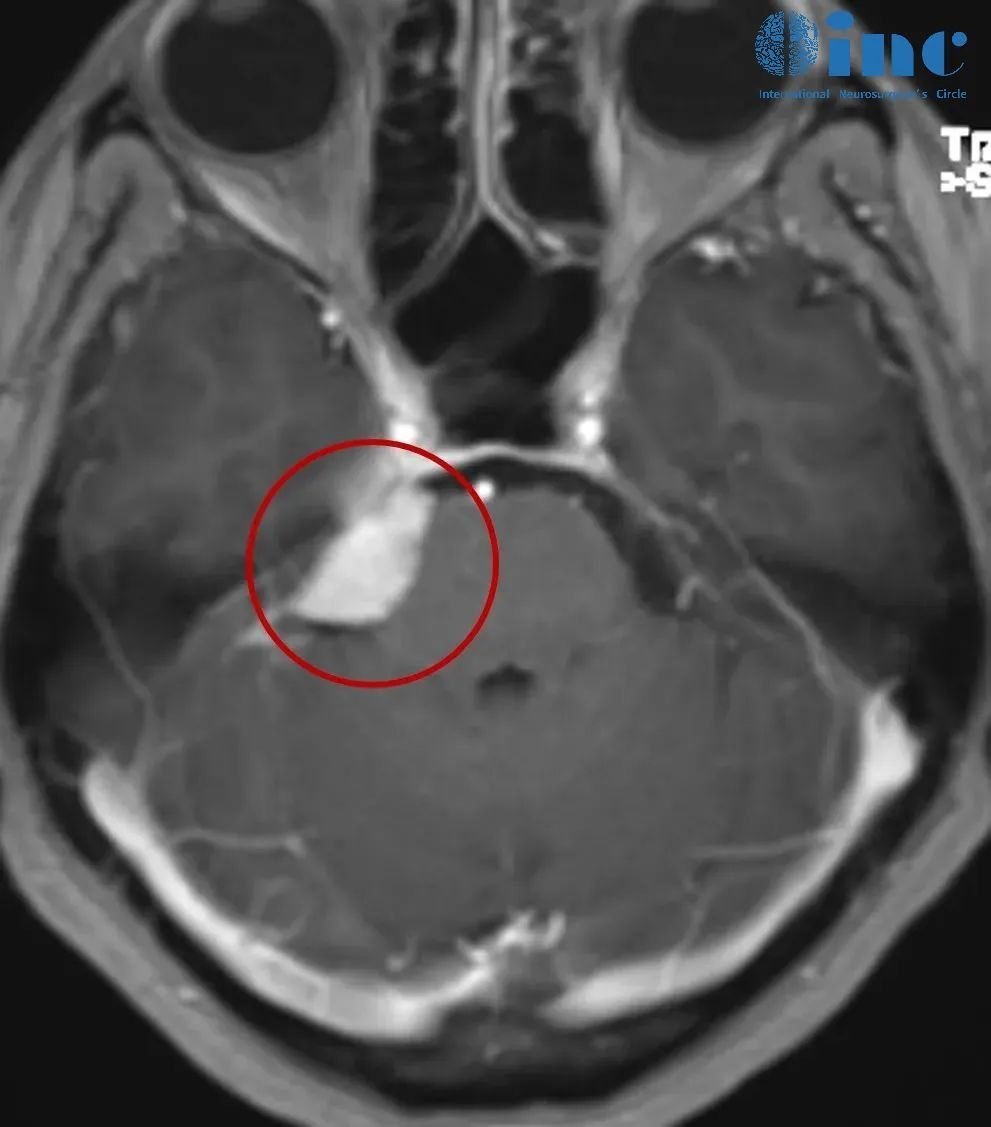

医生告知,右侧桥小脑角(CPA)区占位,肿瘤位置与三叉神经、面听神经、滑车神经等重要颅神经及海绵窦、小脑关系密切,已经压迫到脑干,手术治疗伤及神经的风险很大,也就是说如果手术做不好,可能面瘫、听力丧失、肢体瘫痪,甚至昏迷等。

苦苦的查询之中,他们找到INC巴教授。钟女士在INC的协助下与巴教授展开了咨询,巴教授在详细诊断病情后表示,肿瘤是典型的天幕脑膜瘤(Tentorial meningioma,位于桥小脑角区,是长在大脑与小脑之间硬脑膜隔上的脑膜瘤),侵犯到右侧Meckel腔,瘤体不是很大。如果是初治时,根据肿瘤的位置,大小和患者的年龄等因素,他会建议患者手术。

钟女士2022年1月影像检查结果显示:右侧桥小脑角区占位,肿瘤侵犯到右侧Meckel腔